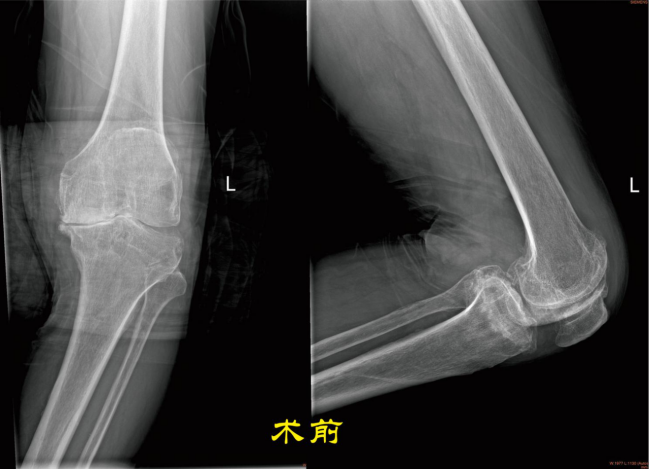

膝骨关节炎主要临床表现:膝关节疼痛,酸胀多见,呈持续性,下蹲起身困难,如上下楼疼痛,不能行走;关节肿胀、畸形,功能障碍。X线片示胫骨平台、股骨髁骨质增生,髁间隆突变尖,关节间隙狭窄。

第三阶段治疗:如果患者膝关节病变集中在单侧,对侧关节里面软骨全层完整,膝关节内外侧副韧带及前后交叉韧带完好,则可行单髁置换术手术。 第四阶段治疗:膝关节内外侧关节软骨均损伤,比如类风湿性关节炎、强直性关节炎、膝关节的感染导致关节软骨破坏感染控制后等等,则需行全膝关节置换术。 (本图:左侧是截骨矫形内固定术后,右侧是全膝关节置换术后) 膝关节骨性关节炎阶梯治疗的有效路径及模式,可达到疾病有效治疗,保护有效劳动力,减少老年人因病致残生活不便引发的社会及家庭医疗负担。